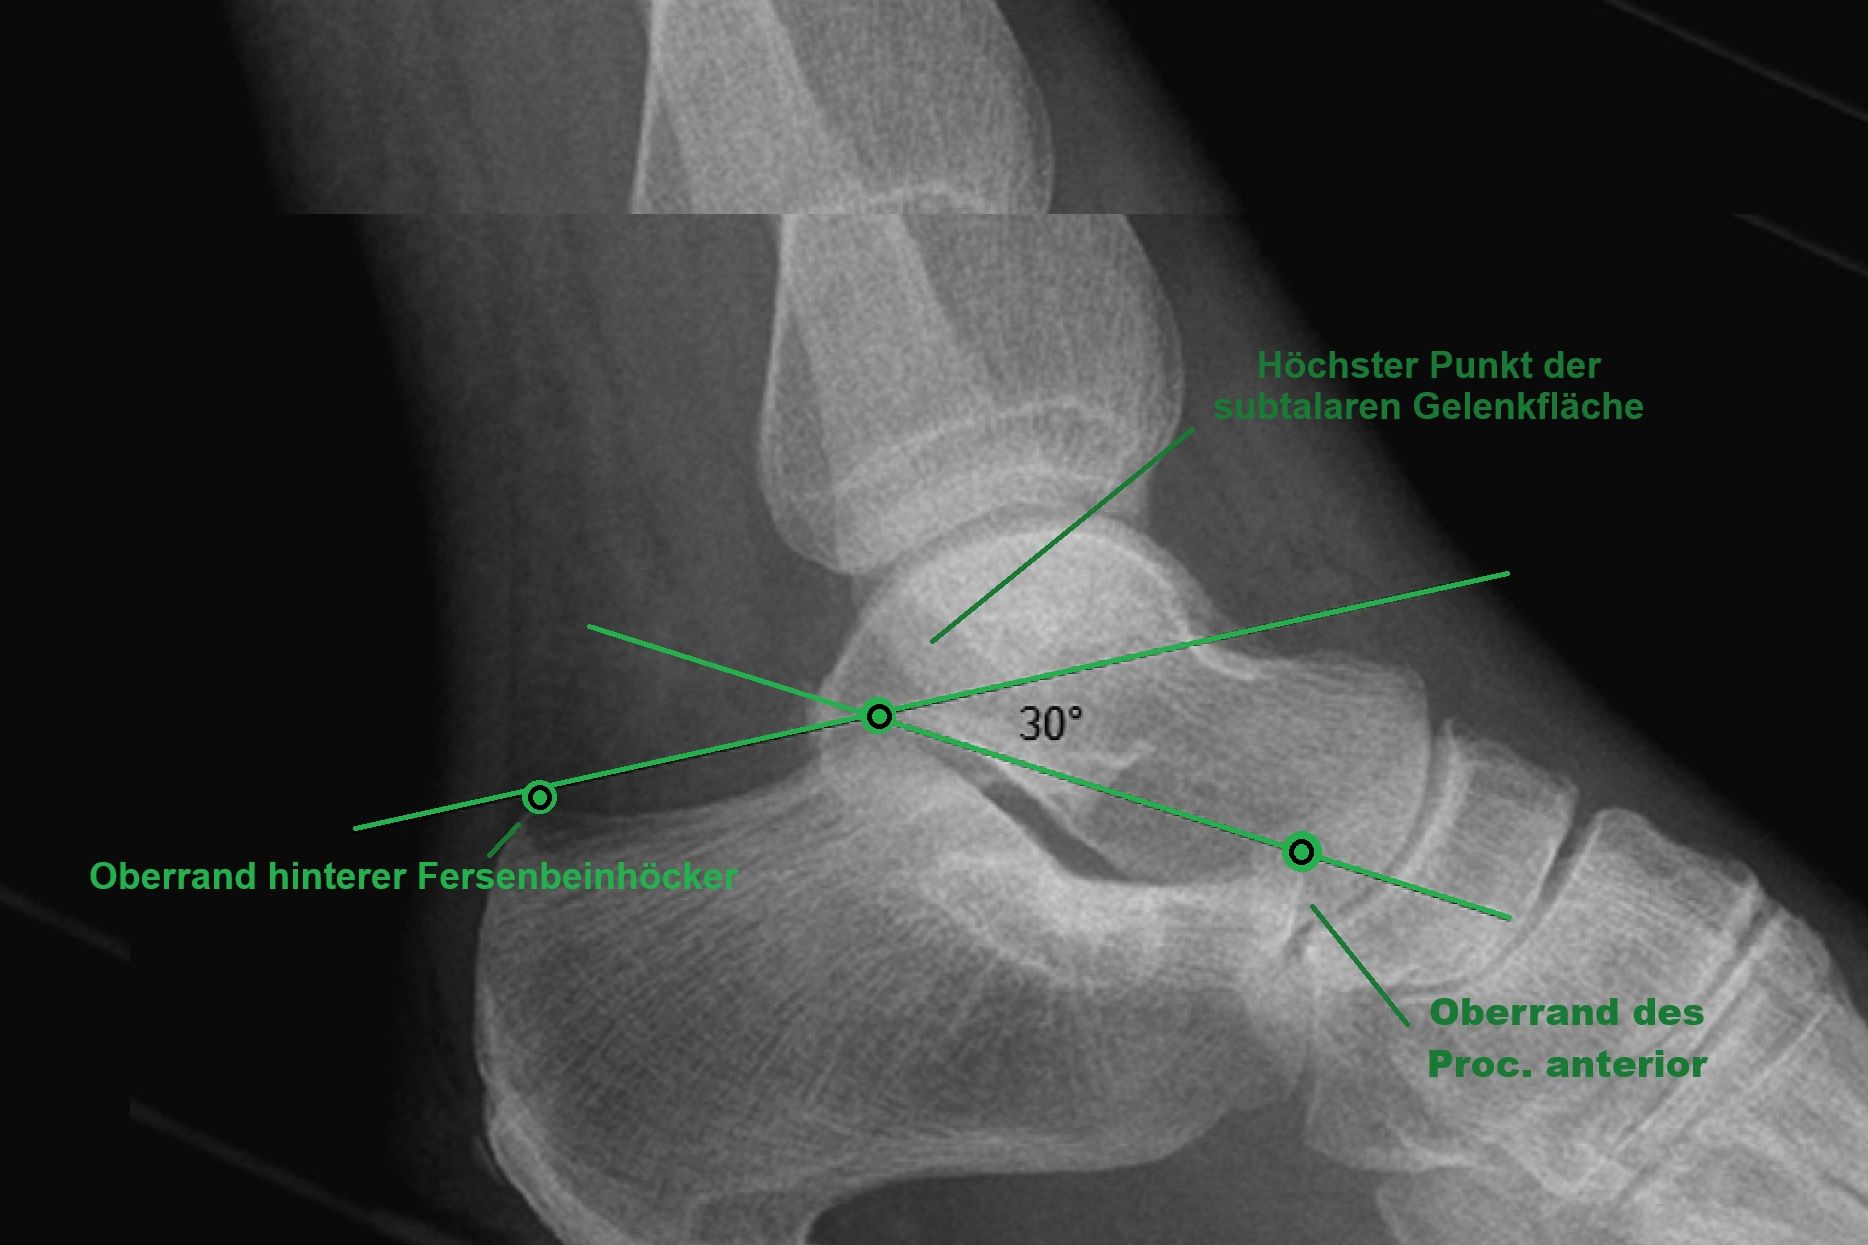

Böhler Winkel

boehler-winkel-normal